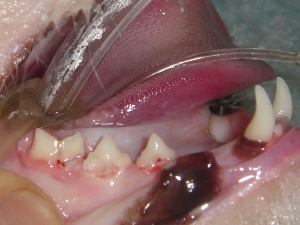

歯石除去 例1